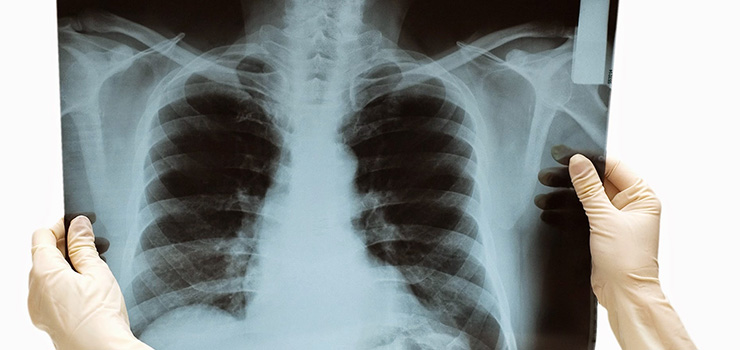

胸部画像検査

長引く咳の原因に肺の病気が隠れていないか画像検査をします。肺炎やCOPD、結核や肺がんなどの病気がないか調べます。

胸部の中に長引く咳の原因となる病気が隠れていないか画像検査で確認をします。肺炎やCOPD、結核や肺がんなどの病気がないかを調べます。